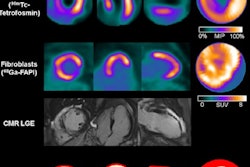

And studies describing new PET radiotracers were also highly engaging, with another of our popular stories from the meeting describing a SPECT/CT tracer that effectively images cardiac amyloidosis.

- SNMMI: New SPECT/CT radiotracer effectively images cardiac amyloidosis

- SNMMI: FAPI PET/CT shows promise in breast cancer staging

- SNMMI: FAPI PET/CT predicts progressive pulmonary fibrosis better than FDG